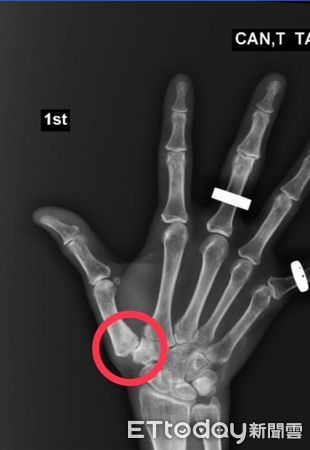

經檢查,曾祥睿醫師發現高姓女子的右手拇指在旋轉時,會因韌帶拉扯而劇痛、活動受限,掌面與背側均有壓痛點。影像及理學檢查後,確診為「拇指腕掌關節炎合併關節半脫位」。由於先前的緩解治療效果不彰,他建議高姓女子醫接受「關節鏡清創及復位手術」,術後疼痛感大幅減輕,拇指活動度恢復良好,已能正常生活並重返職場。